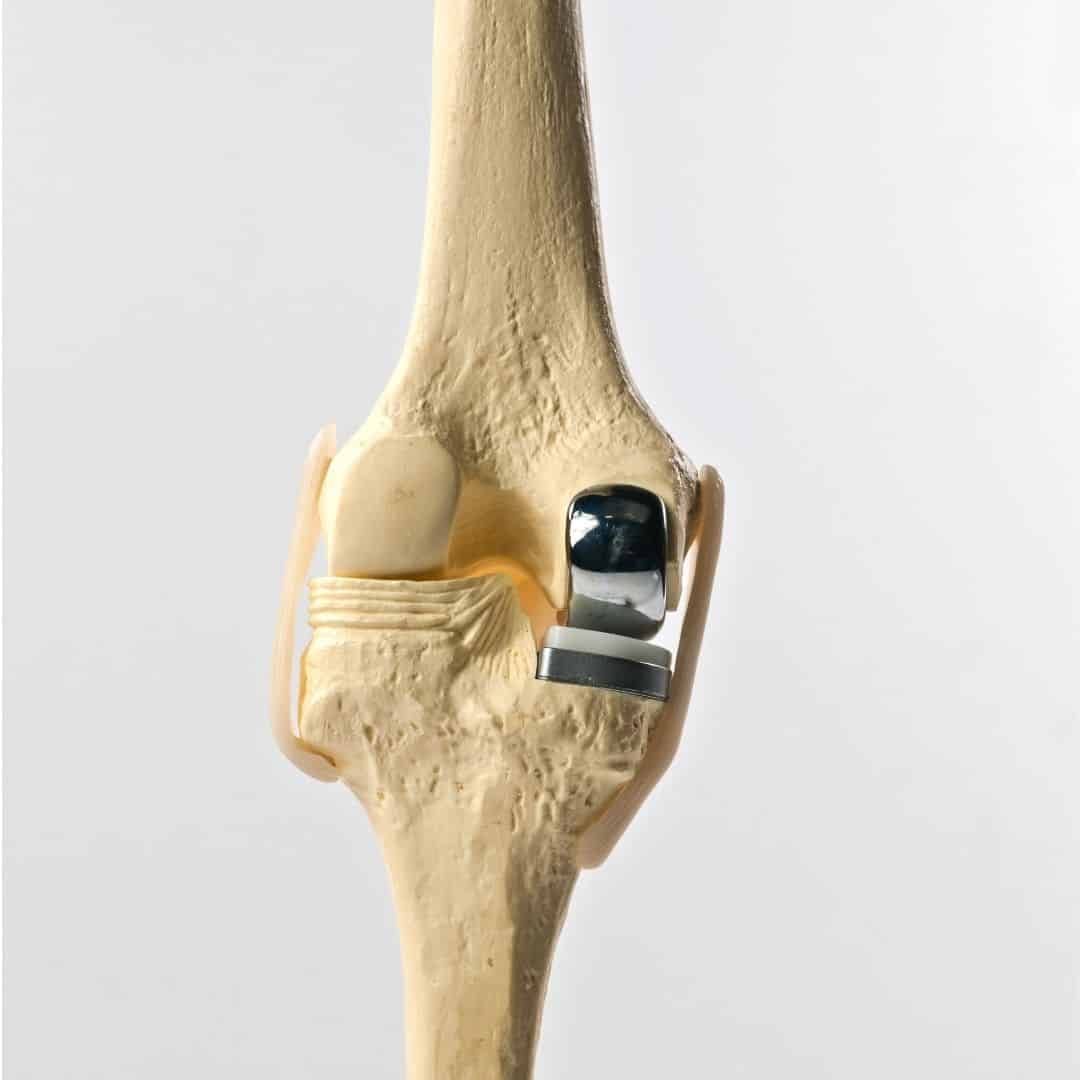

Partial knee replacement, also known as unicompartmental knee arthroplasty, is a surgical procedure aimed at treating arthritis confined to a single compartment of the knee. Unlike total knee replacement, which involves replacing the entire knee joint, partial knee replacement targets only the damaged area, preserving the healthy parts of the knee. This procedure is typically recommended for patients with osteoarthritis that affects only one side of the knee, either the medial (inner) or lateral (outer) compartment, while the rest of the knee remains relatively healthy.

During the surgery, the orthopedic surgeon makes a small incision over the knee and removes the damaged bone and cartilage from the affected compartment. These are then replaced with metal and plastic components designed to mimic the natural movement of the knee. The goal is to relieve pain and improve function while maintaining as much of the natural knee structure as possible. One of the significant advantages of partial knee replacement is that it is less invasive than total knee replacement, resulting in a shorter hospital stay, faster recovery, and less postoperative pain.